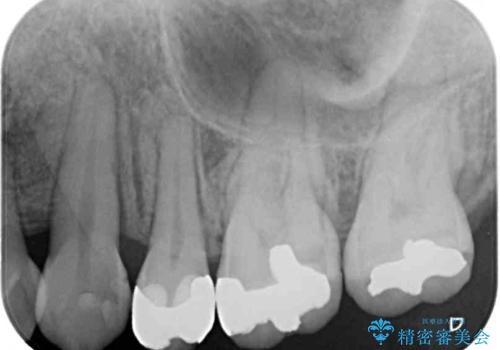

- 他院で抜歯矯正を終えた後、銀色の目立つ奥歯を白くしたいとのことで来院された患者様です。

既にセラミッククラウンが装着されている歯もありますが、不自然な色合いや黒い縁も気になるので、一斉に補綴治療をして統一感を持たせることとしました。

矯正治療を終えたばかりなので、仮歯やセラミッククラウンに置き換えている間に保定がうまくいかなくなる可能性があるため、下顎前歯の舌側を事前にワイヤーで保定しておくこととしました。